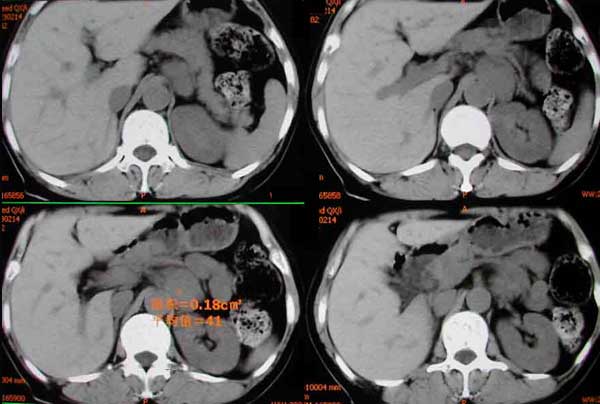

患者女,48岁,10年前右侧嗜铬细胞瘤及右肾切除术后,现血压持续增高。

liyj000发言:结合临床和ct表现:“腹膜后腹主动脉左侧见分叶状软组织块影,边界清,明显强化”可以诊断为嗜铬细胞瘤。

定性大家一致,现在具体定位到底是什么?是肾上腺内?好象不是,有一帧图象上肾上腺受推移,但轮廓存在。所以我说不是肾上腺内的。

不象是来源于左肾上腺。嗜铬细胞瘤约15%发生在肾上腺以外。

术后病理:左侧异位嗜铬细胞瘤